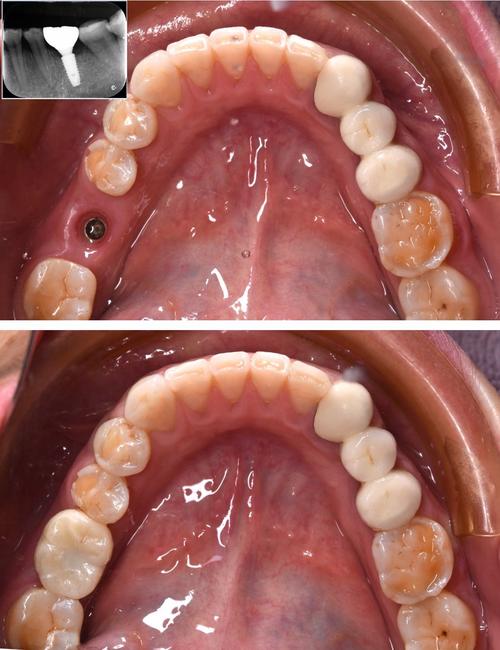

下颌后牙区缺牙后,牙槽骨高度往往减少明显,而上颌后牙区缺牙后,牙槽骨除了高度不足,还可能因上颌窦气化导致骨量“向上空缺”,这类患者通常需要进行植骨,常用方式包括引导骨再生术(GBR)、上颌窦提升术等,通过植入骨材料(如自体骨、人工骨等)恢复牙槽骨的体积和质量,为种植体创造“生长土壤”。

部分患者因初次种植失败(如种植体松动、脱落、周围炎等)后,取出种植体,此时拔牙窝内的牙槽骨可能因炎症刺激或机械损伤而进一步吸收,导致骨量不足,种植体周围炎会导致牙槽骨“溶解”,形成骨缺损,若直接二次种植,可能因骨量不足导致种植体稳定性差。

这类患者需先控制炎症(如牙周基础治疗、抗生素应用),待炎症消退后,通过植骨手术恢复拔牙窝的骨量,常用的植骨材料包括自体骨(如拔牙窝内的碎骨)、人工骨(如羟基磷灰石、β-磷酸三钙)等,植骨后需等待3-6个月,待骨结合完成后再进行二次种植。